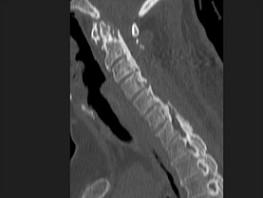

问题 女,58岁,颈部疼痛,活动受限,请结合图像,选出最可能的诊断 ( )

选项 A、椎间盘突出 B、局限性骨化性肌炎 C、颈椎结核 D、椎缘骨 E、颈椎退行性变

答案 E